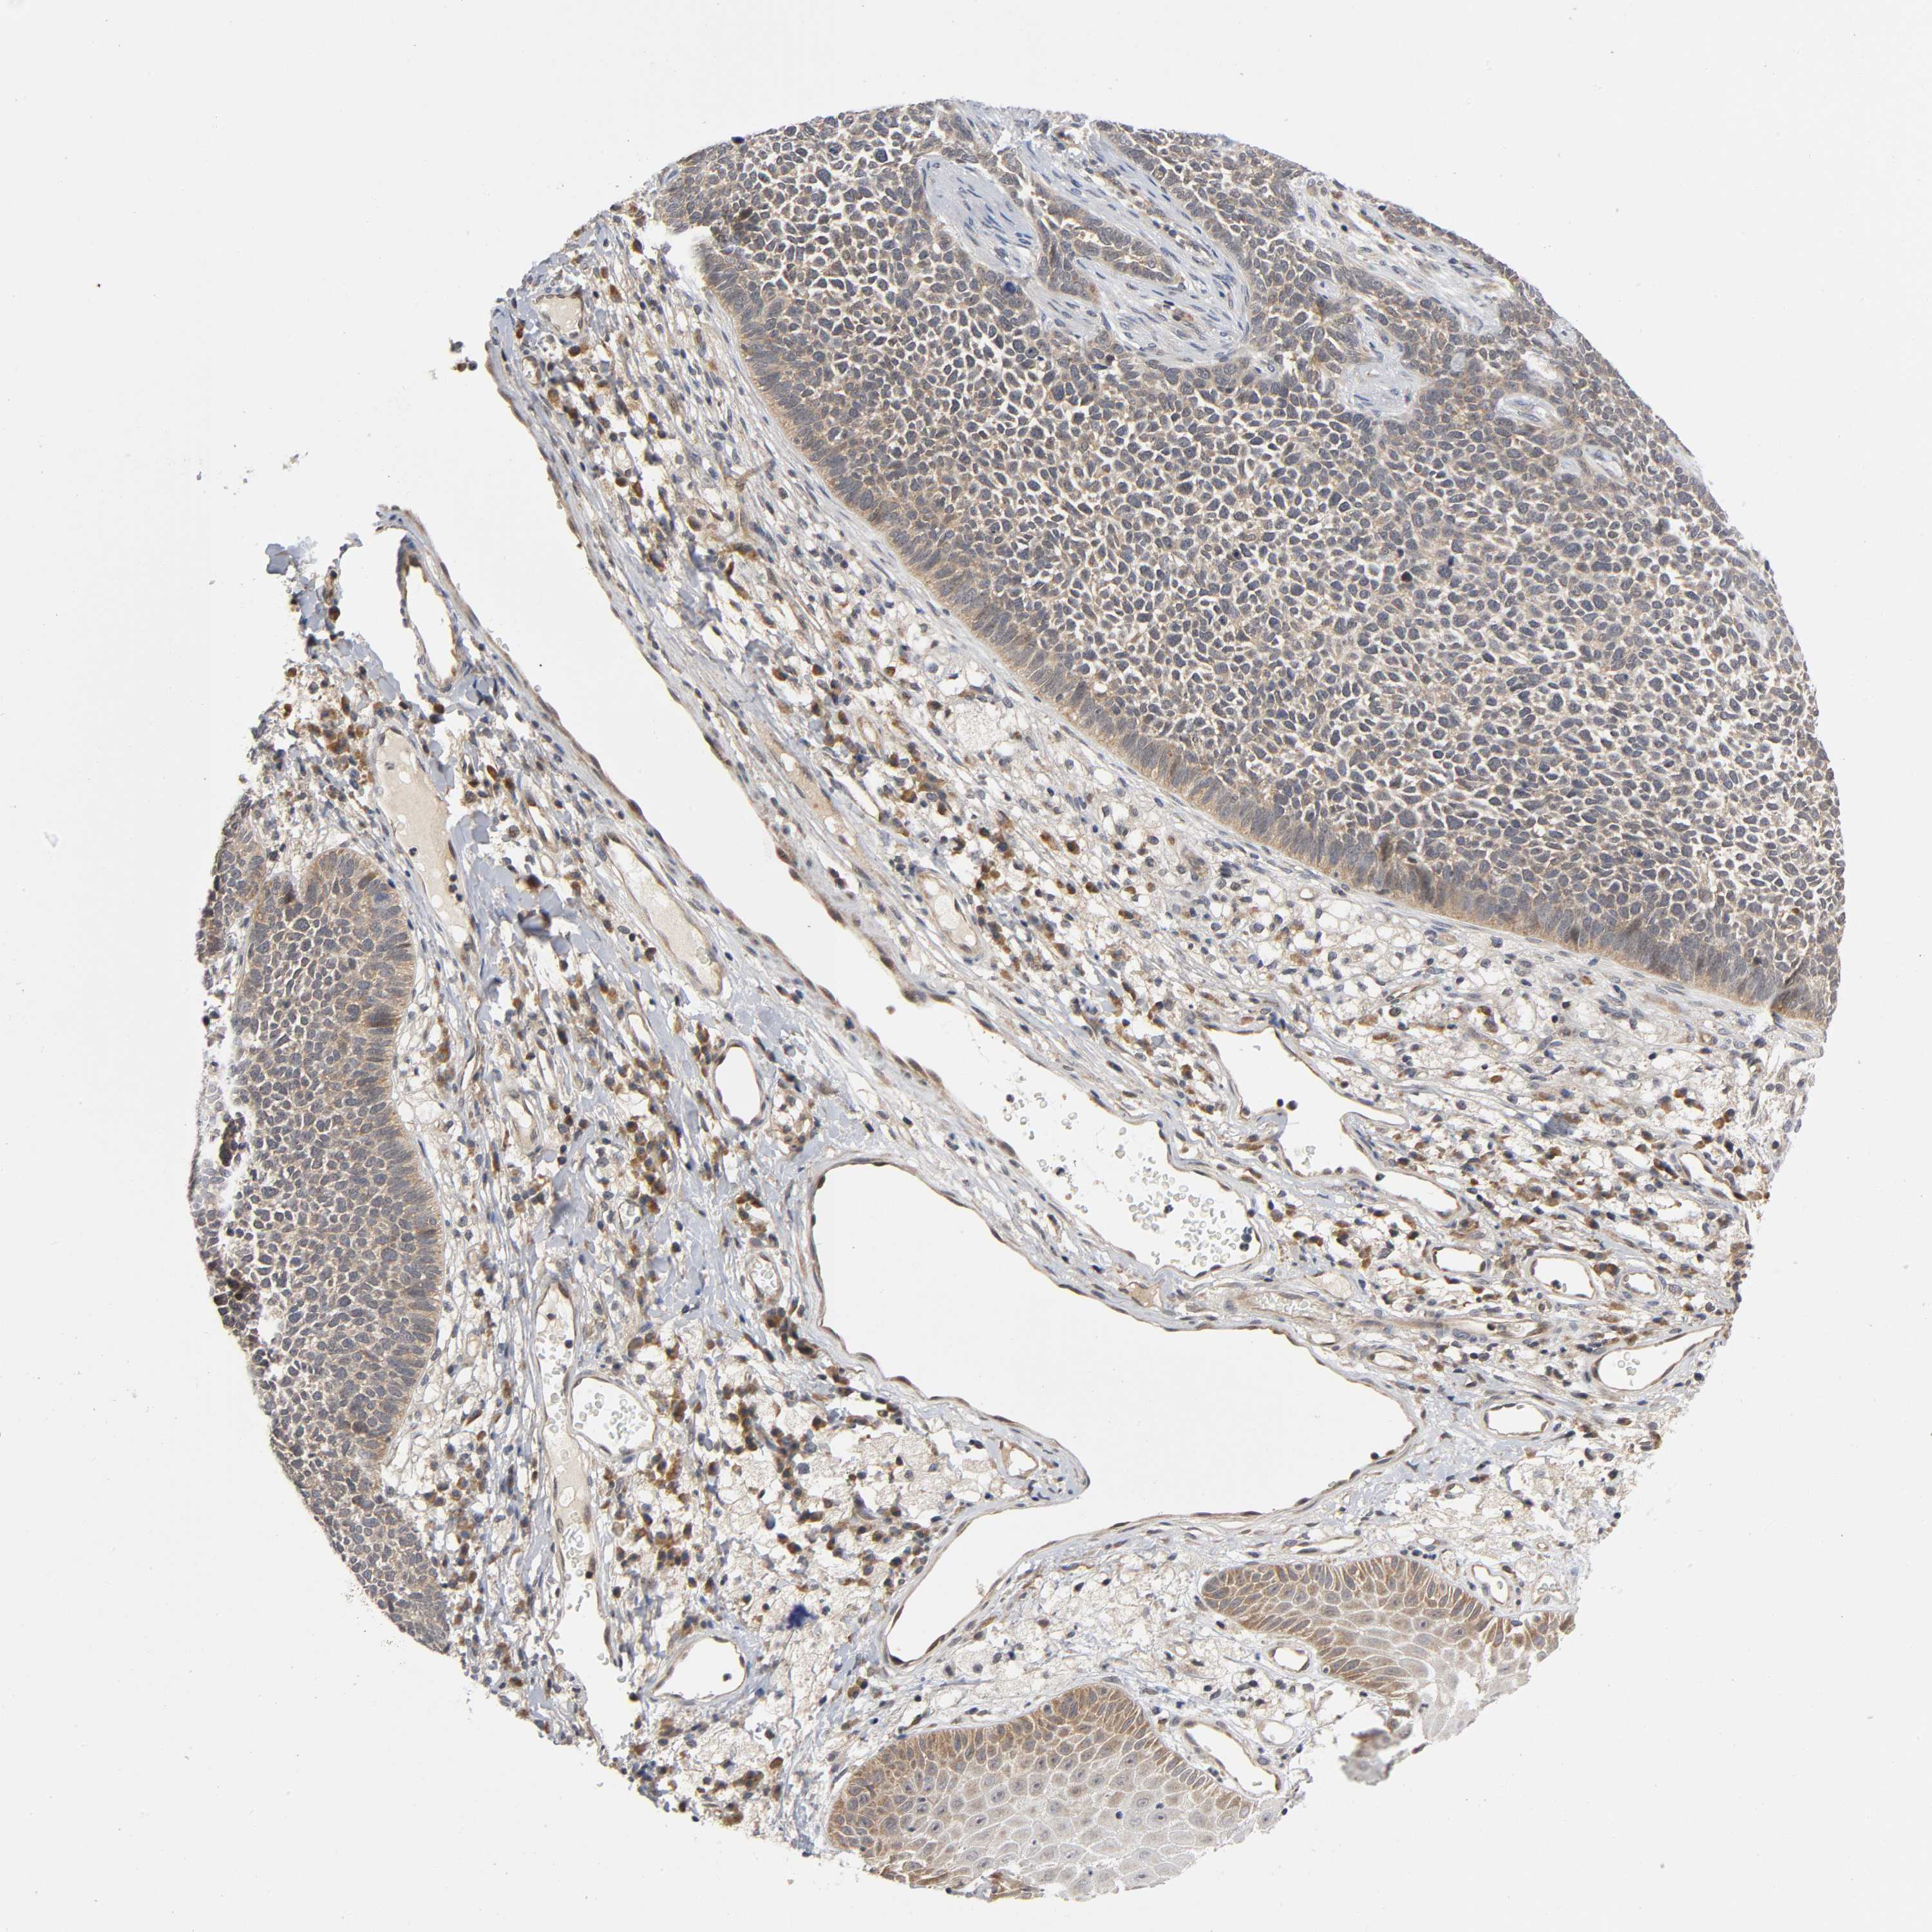

Basal cell and squamous cell cancer

SKIN CANCER - Protein expressioni

A mouse-over function shows sample information and annotation data. Click on an image to view it in a full screen mode. Samples can be filtered based on level of antibody staining by selecting one or several of the following categories: high, medium, low and not detected. The assay and annotation is described here.

Antibody stainingi

Antibody staining in the annotated cell types in the current human tissue is reported as not detected, low, medium, or high, based on conventional immunohistochemistry profiling in selected tissues. This score is based on the combination of the staining intensity and fraction of stained cells.

Each image is clickable and will lead to virtual microscopy that enables deeper exploration of all samples and also displays staining intensity scores, fraction scores and subcellular localization as well as patient and tissue information for each sample.

Antibody CAB004463

Staining

High

Medium

Low

Not detected

Intensity

Strong

Moderate

Weak

Negative

Quantity

>75%

75%-25%

<25%

None

Location

Nuclear

Cytoplasmic/membranous

Cytoplasmic/membranous,nuclear

Squamous cell carcinoma, NOS